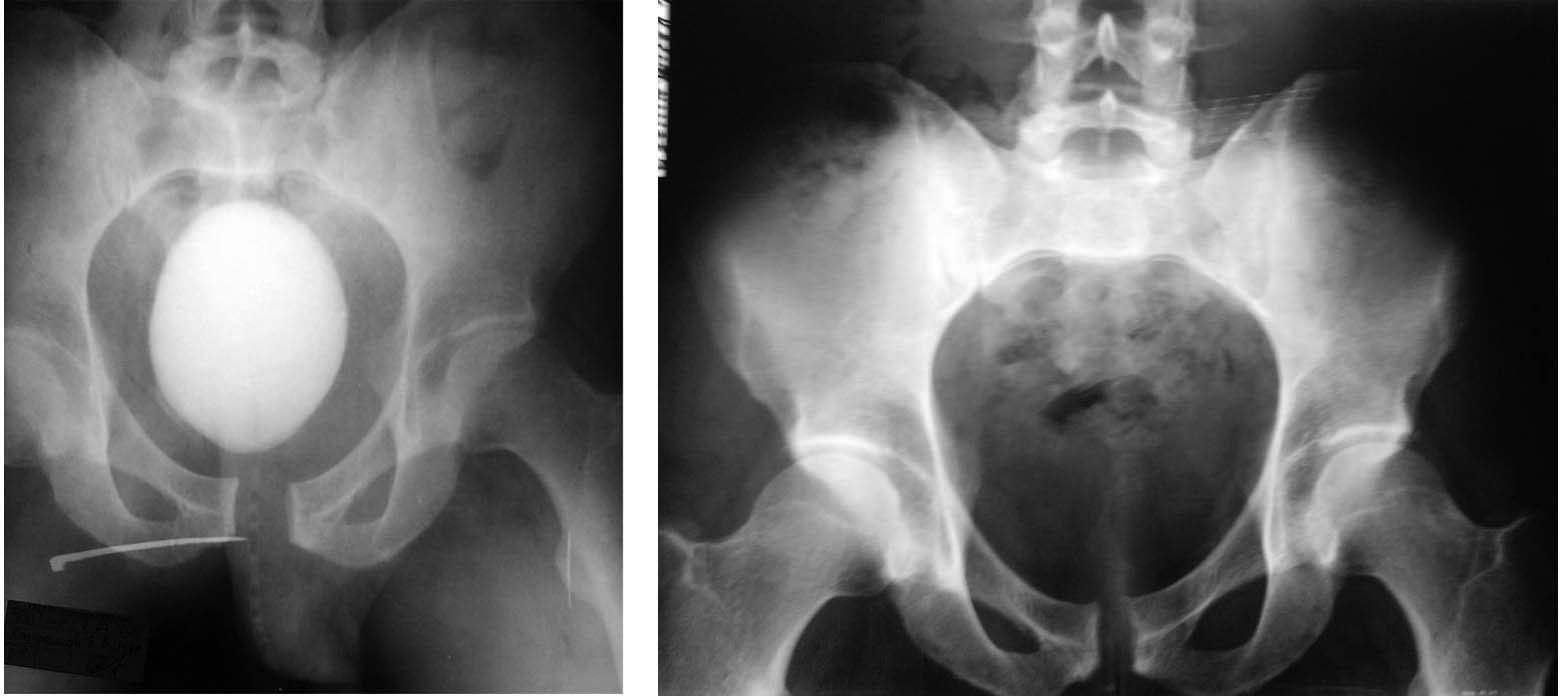

Уважаемые коллеги! Доброго времени суток!Прошу поделиться мнением по такой ситуации. Пациент 35 лет, альпинист, мастер спорта, получил травму 27 мая 2012 года. Уронил на себя камень (как говорят альпинисты, «вытащил чемодан»), получил ротационно-нестабильное повреждение таза – разрыв лонного и частично левого крестцово-подвздошного сочленения, внебрюшинный разрыв мочевого пузыря. Лечился в районной больнице (ближайшей к месту получения травмы) – цистостомия, повреждение таза лечилось консервативно (сначала находился в гамаке), примерно с 4 недели начал активизироваться. В настоящее время ходит без средств опоры, испытывает боли в области левого крестцово-подвздошного сочленения при нагрузке (при нагрузке под рюкзаком, например; без нагрузки, т.е. в обычной жизни, чувствует себя неплохо, болей практически нет), в августе мы вместе с ним прошли альпсборы в горах Киргизии, в общем-то восхождения 2-5 категории он выполнял, но видно, что нелегко, походка изменена (что-то наподобие утиной), сам он отмечает улучшение с тех пор как он начал вставать после травмы, клинически определяется ротационная подвижность левой половины таза в пределах 1-1.5 см, пока не может заниматься своей профессиональной деятельностью (промышленный альпинист), так как не может сидеть в беседке. Цистостома полностью зажила.

Через 3 мес. после травмы под рюкзак- слишком рано! Еще результаты обследования есть: оставшиеся проекции, возможно КТ? Как вариант: пластину на лоно, дополнительно аппарат "передняя рама" недель на 6.

Пластина спереди и всё..., хрящ советую не убирать, так как иначе перезакроете "открытую книгу" и будет большее напряжение на пластину, аппарат я бы не стал, так как диастаз не так велик, репозиционной роли аппарат играть не будет, а перестраховка в плане стабильности, я думаю чрезмерна. На счет того, закрывать ли задние отделы, то есть вводить или нет илиосакральные винты, вопрос дискутабельный при свежей ротационной нестабильности, а вот при застарелой скорее да чем нет. Больше всего опыт у Рункова А.В. Ждем и его совета.....

Открыты остеосинтез передних отделов, хрящ все же лучше убрать почистить края лонных костей до крововточивости - прочнее будет рубец (пластина не может держать вечно). Учитывая сроки после травмы дополнительно сзади провел винт (в свежем случае- нет необходимости, при застарелых - единого мнения нет), можно в процессе установки винта перфорировать зону КПС толстой спицей для формирования гематомы.

Po predstavlennim snimkam ne vidno povrezhdeniya SI joint, skoree transforaminal perelom krestsa. Esli sohranyaetsa rotationnaya nestabilnost - sraschenya ne proizoshlo i tolko perednyaya stabilizatsiya budet bezuspeshnoi - plastina slomaetsa. Neobhodima kombinirovannaya stabilizatsia zadnego i perednego otdelov. No odnaznachnih vivodov po predstavlennim snimkam nelzya - CT taza neobhodimo.

переломы (крестца или подвздошной кости) для такого механизма травмы-вещь нетипичная, необходимы:двухэтапное приложение усилий, например удар, затем падение - windswept или постепенное смещение вектора силы (например перекатывание пешехода под колесами автомобиля). при переломах картина немного другая, есть сгибание половины таза, бывает,что с захождением.